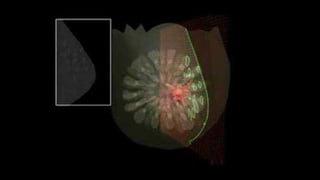

• RM mamaria

• Anormalidades de tejidos blandos locales

• Evaluación de lesiones ocultas, multifocales o bilaterales

• Respuesta a neoadyuvancia (previa y posterior)

• Cirugía conservadora en pacientes de alto riesgo.

• Reconstrucción mamaria previa (biopolímeros, implantes)